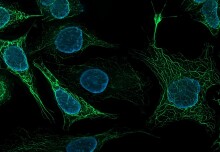

Shape-shifting cancer cell discovery reveals potential skin cancer drug targets

A new technique allows scientists to see cells in 3D, and determine how different genes affect the shapes they adopt.

Shape-shifting cancer cell discovery reveals potential skin cancer drug targets

A new technique allows scientists to see cells in 3D, and determine how different genes affect the shapes they adopt.